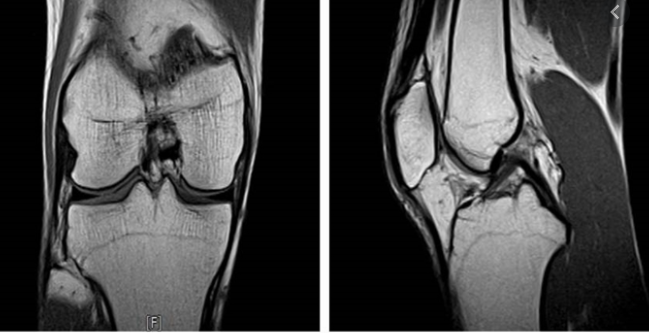

하지만 금액이 부담이 가더라도 의심되는 증상이 있다면 미리미리 검사를 받아 병을 키우지 않는것이 좋다고 생각합니다. 그렇기 때문에 무분별한 검사보다는 전문의 진료를 통해 정확한 검사를 시행하는 것이 좋습니다.

그리고 내년부터는 보장성강화를 위해 건강보험공단에서 복부 및 다른 부위에도 MRI 적용을 위해 제도 개선을 실시 중이라고 합니다.